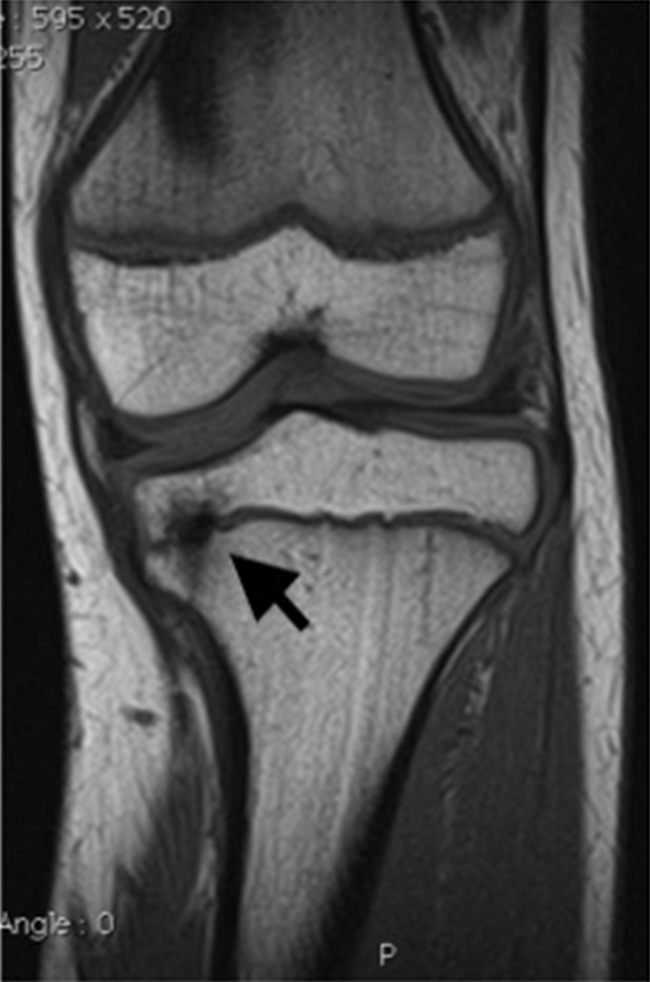

Dans la classification de Salter et Harris (figure 115.2), le trait de fracture part toujours du cartilage de croissance. Cette classification a valeur pronostique surtout au membre supérieur. Plus le stade est élevé, plus le risque de fermeture prématurée du cartilage (épiphysiodèse) est important. Plus l’enfant est jeune, plus cette fermeture du cartilage pourra induire des répercussions orthopédiques (raccourcissement, angulation) (figure 115.3). Les fractures diaphysaires incomplètes sont de bon pronostic.

Fig. 115.3 IRM du genou gauche d’une enfant de 12 ans adressée pour varus du membre inférieur gauche. Séquence coronale T1. Varus tibial gauche lié à un pont d’épiphysiodèse proximal médial tibial (flèche) post-traumatique.

Source : CERF, CNEBMN, 2022.